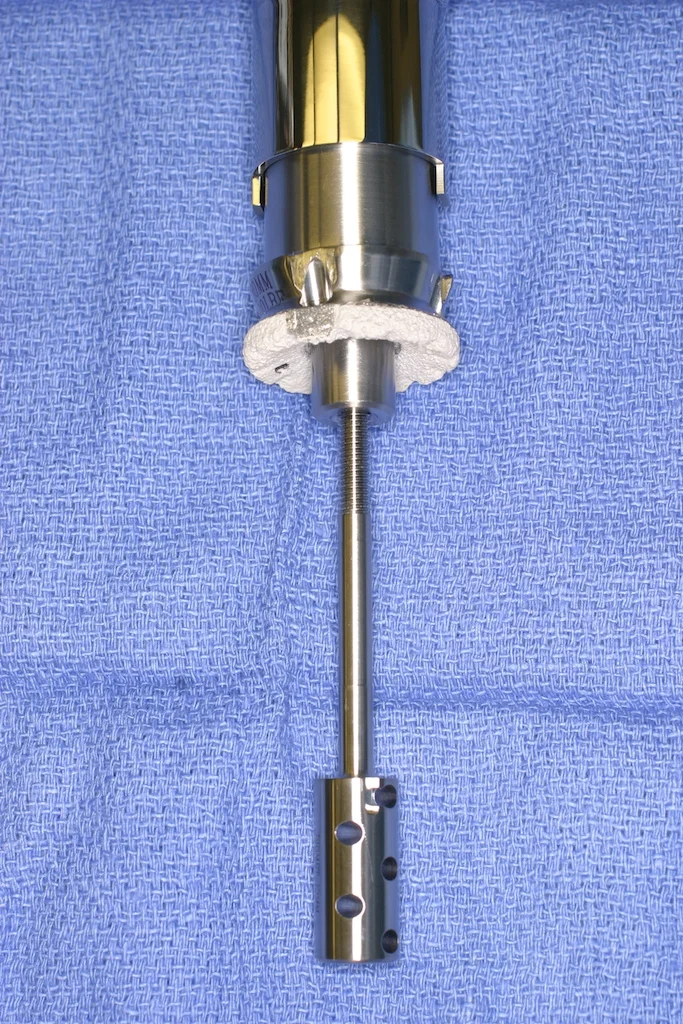

Endoprosthetic design has advanced tremendously and now off-the-shelf implants can be used to reconstruct almost any bone defect. The implants are “modular”, meaning they are assembled at the time of surgery from component pieces.

When a bone tumor affects a child, not only must the surgeon reconstruct the missing bone, but must also plan for the child’s future growth. In these cases, an expandable endoprosthesis can be used. These implants are designed to be lengthened after being implanted inside the child. This expansion is done periodically via a minor surgical procedure as the child grows, keeping up with the growth of the other leg. Depending on how many years of growth the child has before reaching skeletal maturity, the original endoprosthesis may or may not need to be exchanged for a larger one as the child gets older.